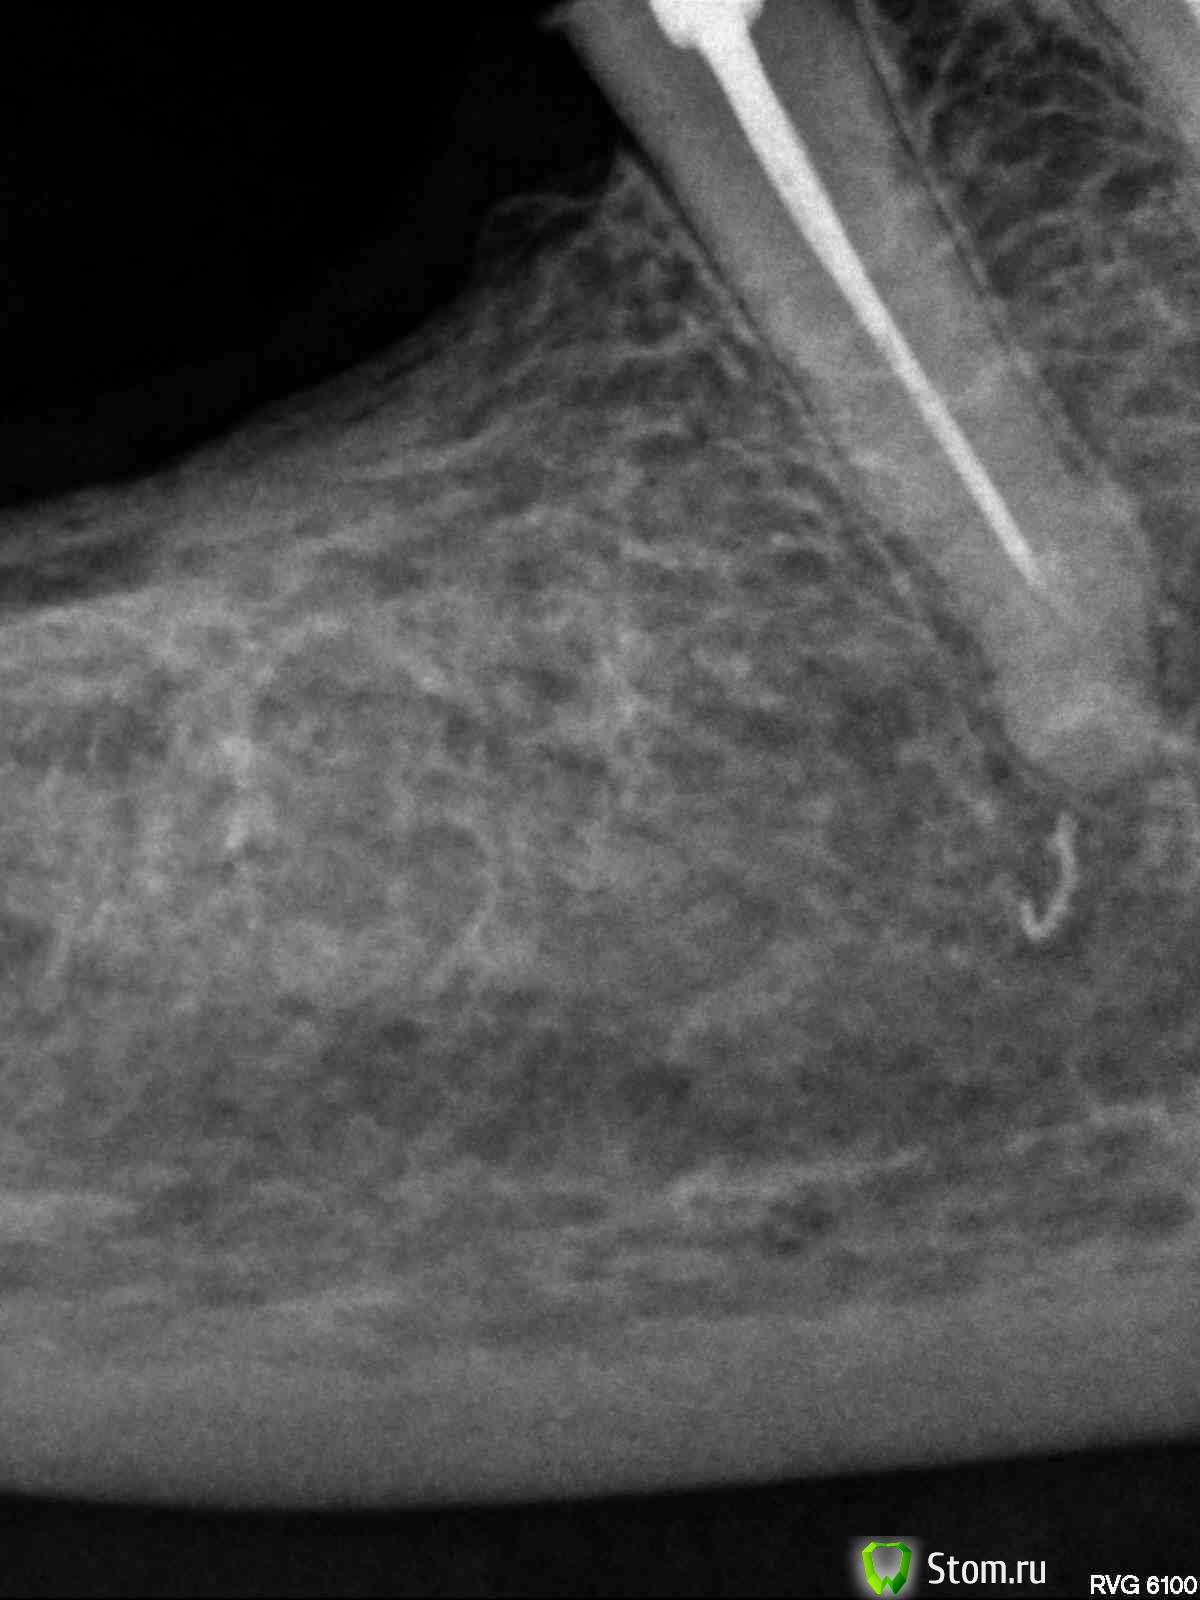

evm Опубликовано 26 апреля, 2012 Поделиться Опубликовано 26 апреля, 2012 Здравствуйте! Проблема: на живых 3-ке, 4-ке и 5-ке внизу справа стояла металлопластмасса (мост полуразрушенный, травмировал десну). Хотела менять осенью, но, поскольку стали появляться ночные ноющие боли (терпимые, но с Метрогилом-Дента), решила не тянуть. 28 марта под анестезией депульпировали все три зуба и запломбировали. Когда пломбировали, в 5-ке чувствовала боль и потом было больно по ней стучать. 10 апреля должна была уже начать протезирование (металлокер. на штифтах). 3 и 4 молчали, а 5-ка все время мозжила и к 10 апреля поддала жару- воспалился лимфоузел и боль усилилась, а также появился болезненный участок рядом с корнем. Канал открыли, положили лекарство под временную пломбу, через три дня - повторили. Терапевт все время убеждала, что с зубом полный порядок. Другой врач сказала: или аллергия, или периодонтит на маленьком учаске (в узкой щели), где тяжело достать (это мой вольный пересказ ее слов). Боль если и утихала, то очень медленно и зуб чувствовала всегда. Через три с половиной недели (22 апреля) взбесилась 4-ка, больно было толкать языком и болела больше, чем 5 (возможно, из-за замерзших накануне ног). Поскольку первый врач считал, что у меня все вылечено, пошла ко второму. Та сделала укол (антибиотик плюс ультракаин, на лидокаин была раньше алергия - крапивница по всему лицу, как герпес), вспомнили мы про физлечение, и в своей поликлинике стала делать дэнос и атерм.УВЧ. Опять пошла алергия, сначала думала - на инъекцию, а теперь думаю, может быть и на ток - пузыри кучно в месте контакта с электродом, а на лидокаин до этого - по всему лицу. Пока все отменили. Зубы периодически о себе напоминают. По 4-ке стучать больнее, чем по 5-ке. 4-ку не открывали. Аллергия (тогда почему 3-ка молчит?) или хр.периодонтит? На снимке видно, что у 5-ки пломб.материал вышел за верхушку, но, скорее всего мозжащая (а иногда пульсирующая, но спать дающая) боль не из-за этого? Ссылка на комментарий

Magdalena Опубликовано 29 апреля, 2012 Поделиться Опубликовано 29 апреля, 2012 Если подвела антисептическая обработка каналов, что Вы предлагаете делать мне? Перелечивать не только 5 зуб, но и 4. Видимо, диагностика по снимкам затруднена, пока нет патологии в виде гранулем и кистОбычные прицельные снимки - двухплоскостные, по ним не всегда видно локализацию воспалительного процесса, ход и количество корневых каналов. Поэтому для более точной диагностики существует компьютерная 3Д - томография (трехмерная), на ней зуб можно "покрутить" и посмотреть со всех сторон, а также в поперечном срезе (это помогает определить кол-во и ход каналов). Ссылка на комментарий